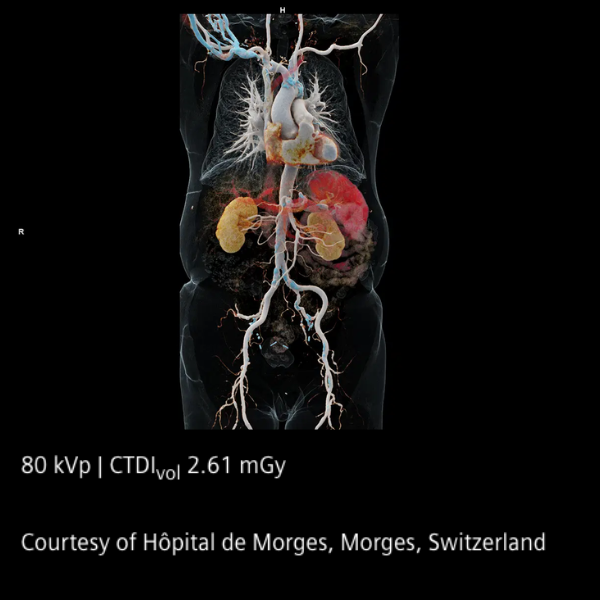

En el corazón del sistema se encuentran los detectores QuantaMax, capaces de medir cada fotón individualmente y convertirlo directamente en señal eléctrica. Esto permite eliminar el ruido electrónico, mejorar la relación contraste/ruido y obtener imágenes de alta resolución espectral sin aumentar la dosis de radiación. La combinación con la tecnología Dual Source y el potente tubo Vectron X-ray garantiza un rendimiento excepcional incluso en pacientes con alto índice de masa corporal.

El NAEOTOM Alpha ofrece velocidades de escaneo ultrarrápidas y una resolución temporal nativa de 66 ms, ampliando las posibilidades clínicas en cardiología, oncología, neurología y estudios complejos. Sus flujos de trabajo asistidos por inteligencia artificial optimizan la operación y apoyan la toma de decisiones clínicas.